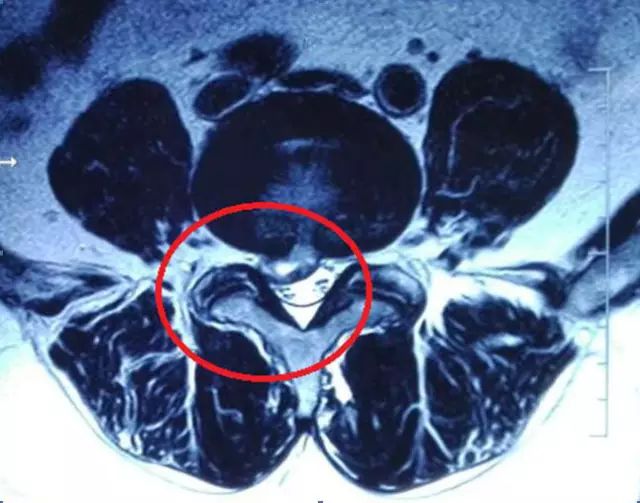

那么,节育环是否会产生伪影呢?这一点确实是真的,它确实会产生一些伪影并影响周围组织的图像质量。但是这种影响是局限在盆腔的,对于腰椎以及颈椎的核磁共振不会产生影响。以我今天门诊的一名50岁女性椎间盘突出患者为例,大家可以看到,X线片上显示盆腔里有金属节育器,在她的磁共振片子里,节育器确实产生了少量伪影,但是椎间盘突出的部位仍清晰可见,伪影未造成任何干扰,丝毫不影响医生的读片判断。